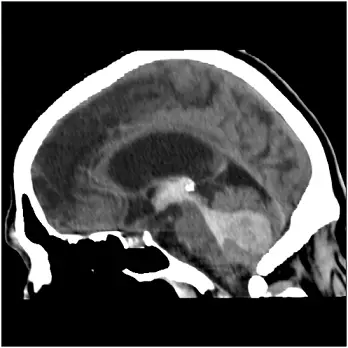

一位 68歲男性於早上被家人發現臥於床上叫不醒,枕頭與嘴邊有嘔吐物,送來急診時昏迷指數為 E1V1M4 ,血壓196/103 mmHg,心跳 72/min ,電腦斷層檢查如圖,下列敘述何者正確?

影像分析:

從非造影電腦斷層檢查(CT)軸位可見中央橋腦區密度明顯增高,呈齒狀或愛心樣形態,周圍腦組織被壓迫但未見跨向硬腦膜下或硬腦膜外的血腫,也無顱骨骨折線。本題第二張影像(矢狀面)更清楚顯示出血位於橋腦中央,並部分延伸至第四腦室,但未累及大腦半球皮質。此為典型高血壓性pontine hemorrhage,中樞橋腦出血常迅速影響呼吸與意識功能。